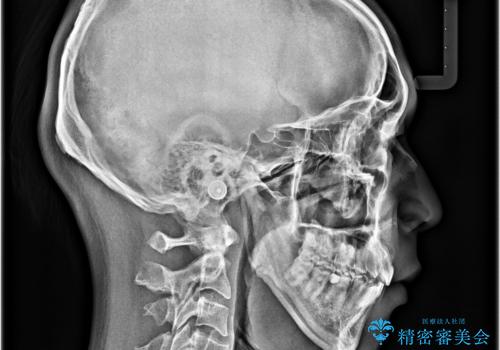

舌の突出癖などにより上顎前歯が前方に突出し、さらに歯列幅が狭小になっている状態でした。

また、上顎歯列全体が下顎に対して前方位に位置していました。

上顎歯列幅を側方に拡大するとともに、歯列全体を後方に移動させるためのアンカースクリューと補助装置を使用し、上顎左右第一小臼歯2本、下顎左右第二小臼歯2本、計4本を抜歯し、ワイヤー装置にて矯正治療を行うこととしました。

上下前歯の前後差が非常に大きく、3年以上の治療期間が予想されましたが、無事に3年間ちょうどで仕上げることができました。